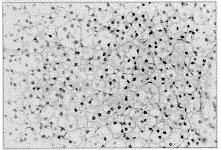

术中所见:在左腹股沟管内找到左侧输精管,其末端为一盲端,位于左腹股沟管中部。紧邻盲端尖部有一约3 mm×2 mm×2 mm大的白色结节,疑为发育极差之睾丸,未见附睾及精索。沿腹股沟管向上探查腹膜后并打开内环口上方腹膜探查腹腔,均未找到精索,故切除上述可疑结节送病理,常规逐层缝合切口,结束手术。术后病理报告:异位肾上腺组织(图1)。

图1 左腹股沟异位肾上腺组织 HE×500

Figure 1 Ectopia adrenic tissues, left inguinal HE×500